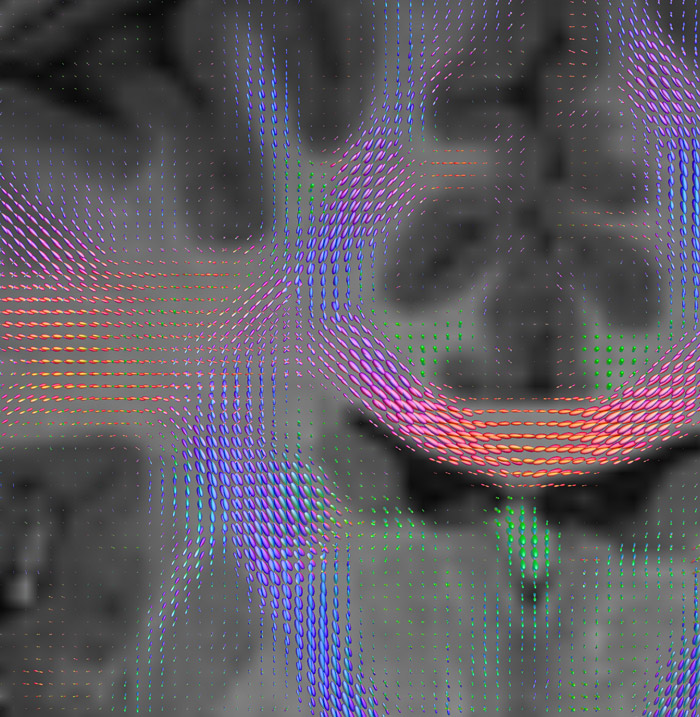

CSD of multishell DWI results in the white matter FOD at each voxel. Unlike the conventional diffusion tensor model, this approach enables accurate modeling of multiple fiber populations within a single voxel.

Crossings of the corpus callosum, corticospinal tracts, and the superior longitudinal fasciculus are shown.

All images were created from the same acquisition in a child using Ingenia 3.0T CX and 32-channel dS Head coil. Diffusion data was acquired at b-values 0, 500, 1000, 2000, 3000. The use of high b-values (3000 s/mm2) effectively suppresses extra-axonal water signal and provides high angular resolution.

Data processing was performed using open source software. Fiber tracking was performed using the MRtrix package (J-D Tournier, Brain Research Institute, Melbourne, Australia, https://github.com/MRtrix3/mrtrix3), Tournier et al. 2012. DEC TDI based on F Calamante et al 2010.